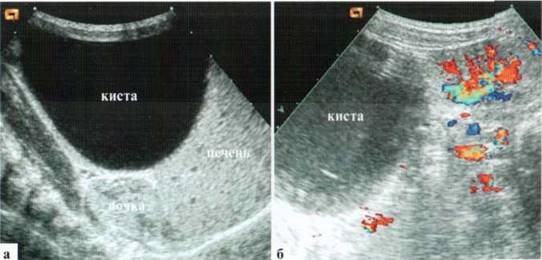

Ребенок переведен из роддома на 2-е сутки жизни с антенатально тестированным кистозным образованием в животе. При поступлении состояние удовлетворительное, пальпаторно образование не определяется.

ПЕЧЕНЬ — топография не изменена, размеры правой доли — в пределах возрастной нормы, левая — частично экранирована содержимым желудка, визуализируемые фрагменты внутрипеченочных сосудов и желчных ходов — не дилатированы.

ЖЕЛЧНЫЙ ПУЗЫРЬ - визуализируется достоверно, содержимое жидкостное, в небольшом количестве (ребенок осмотрен после еды).

ПОДЖЕЛУДОЧНАЯ ЖЕЛЕЗА - визуализируется фрагментарно, структура визуализируемых фрагментов эхографически не изменена.

ЖЕЛУДОК и ДВЕНАДЦАТИПЕРСТНАЯ КИШКА - большое количество содержимого в просвете.

ПОЧКИ: топография, размеры не изменены. Физиологическая подвижность сохранена. Контуры ровные, четкие, сохранены. Структуры хорошо дифференцированы. Паренхима гомогенная, толщина в пределах возрастной нормы. Гидронефротических изменений, интра- и параренальных патологических включений не выявляется.

НАДПОЧЕЧНИКИ: топография, размеры, структуры не изменены.

МОЧЕВОЙ ПУЗЫРЬ — опорожнен, достоверная эхографическая оценка органов малого таза невозможна.

В правых отделах брюшной полости определяется расположенное на уровне пупка, соприкасающееся с вентральной поверхностью печени округлой формы образование с неровными контурами размерами около 54x34x50 мм. В просвете — мелкодисперсная взвесь, тонкие септы и содержимое средней эхогенности, фиксированное, с неровными, «ворсинчатыми» контурами (рис. 2.18). Эхографическая картина может быть расценена, как проявления кисты яичника, возможно — антенатальный перекрут (?).

ИНТРАОПЕРАЦИОННОЕ ПОДТВЕРЖДЕНИЕ

Рис. 2.18. Эхограммы и интраоперационный снимок: антенатальный перекрут и самоампутация кисты